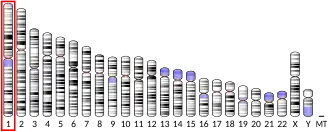

NLR family pyrin domain containing 3 (NLRP3) (previously known as NACHT, LRR, and PYD domains-containing protein 3 [NALP3] and cryopyrin), is a protein that in humans is encoded by the NLRP3 gene[5] located on the long arm of chromosome 1.[6]